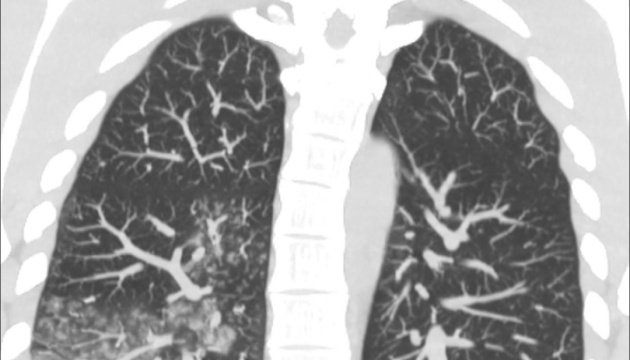

За її даними, рентгенологічні зміни неспецифічні: «матове скло», ателектази, гіперактивні легені, іноді – консолідація. Частіше двосторонні ураження (як на фото).У світі важким хворим застосовують інгаляційний рибавірин (зауважте – емпірично, оскільки доказів немає зі зрозумілих причин). У нашій країні така форма рибавірину не зареєстрована, а таблетована навряд чи буде ефективною, ґрунтуючись на нашому досвіді, пояснює інфекціоністка.